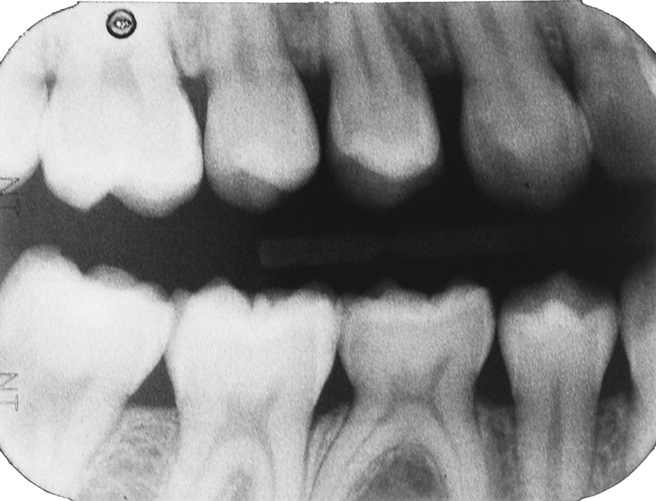

Fig 3. Three thin soft dental picks were used simultaneously for SDF proximal surface saturations in a teenaged patient (Fig 3). After 60 seconds, the treated regions were covered with 5% fluoride varnish (Fig 4). A comparison can be seen of pre-SDF-treatment bitewing films (Fig 5) and 8-month post-SDF bitewing films (Fig 6) for the patient shown in Fig 3 and Fig 4. Radiolucencies were similar or improved, except for contact of maxillary first and second molars.

Fig 5. Three thin soft dental picks were used simultaneously for SDF proximal surface saturations in a teenaged patient (Fig 3). After 60 seconds, the treated regions were covered with 5% fluoride varnish (Fig 4). A comparison can be seen of pre-SDF-treatment bitewing films (Fig 5) and 8-month post-SDF bitewing films (Fig 6) for the patient shown in Fig 3 and Fig 4. Radiolucencies were similar or improved, except for contact of maxillary first and second molars.

Fig 6. Three thin soft dental picks were used simultaneously for SDF proximal surface saturations in a teenaged patient (Fig 3). After 60 seconds, the treated regions were covered with 5% fluoride varnish (Fig 4). A comparison can be seen of pre-SDF-treatment bitewing films (Fig 5) and 8-month post-SDF bitewing films (Fig 6) for the patient shown in Fig 3 and Fig 4. Radiolucencies were similar or improved, except for contact of maxillary first and second molars.

Interproximal insertion of SDF is demonstrated in different patients in Figure 3 through Figure 11. Various diameters and brands of soft dental picks may be used depending on the closeness of the proximal surfaces and ease of insertion; for example, some picks are designed for use in wider spaces between teeth. This protocol also offers versatility. Figure 3, for example, shows the simultaneous use of three thin soft dental picks to saturate proximal surfaces with SDF in a teenaged patient; the treated regions were subsequently covered with fluoride varnish (Figure 4). This patient was initially treated in April 2019 (Figure 5), with an identical re-application 3 months later. As shown in Figure 6, the December 2019 bitewing film revealed good results with the possible exception of the contact regions of the maxillary first and second molars. New SDF application was completed in the December appointment.

The senior author's (TPC) private practice experience with soft-tip insertion of SDF into contacting proximal surfaces of teeth is that most beginning proximal surface caries lesions cease to progress, as evidenced by subsequent bitewing radiographic comparisons (Figure 3 through Figure 6, Figure 12 through Figure 18). The chances for success vary, however, depending on frequency of application, subsequent flossing by patients or adults flossing younger children, diet control, individual mouth chemistries, and use of fluorides for the topical effect. It must also be emphasized that office staff should make extensive efforts to inform children and parents that subsequent daily flossing is needed to accompany SDF treatments; otherwise, SDF applications will only delay the inevitable progression of caries. Flossing methods should be demonstrated for patients and for parents so they may see how to floss younger children. Showing them enlarged graphic photographs of flossing results may be helpful in this regard. Parents and patients should be made aware that if interproximal dental plaque accumulations persist without daily interruption by flossing, the acid insult will eventually take its toll on the proximal surfaces and caries lesions will progress to the point where restorative intervention may be required.